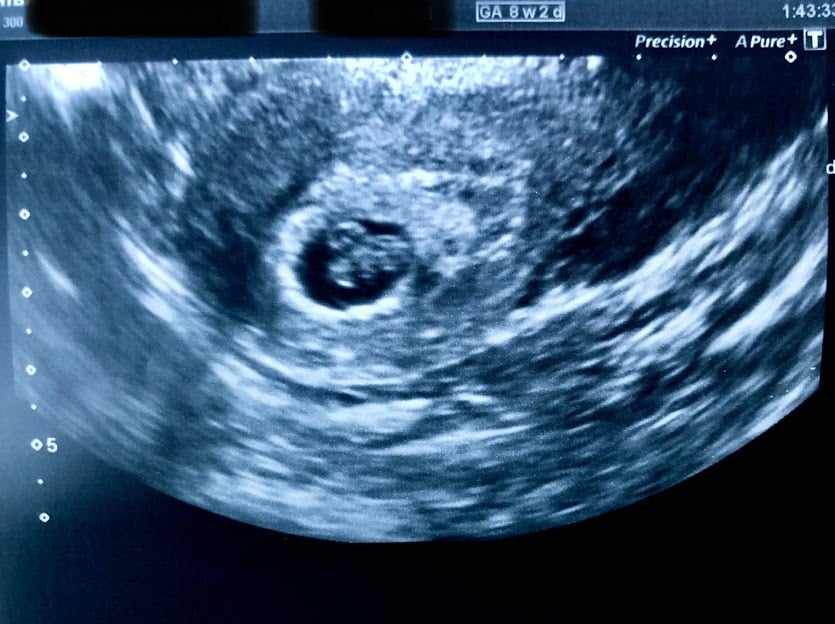

We had our first ultrasound yesterday and got to hear that sweet, sweet heartbeat. I swear that sound will never get old. I was allowed to take a 10 second clip to send to MH and I listen to it on repeat. Heartbeat of 134, measuring 4 days ahead at 8w2d.